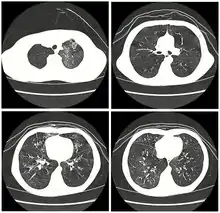

| High resolution CT scan showing bronchiolitis obliterans with mosaic attenuation, bronchiectasis, air trapping and bronchial thickening[3] | |

Early in the disease chest radiography is typically normal but may show hyperinflation.[6] As the disease progresses a reticular pattern with thickening of airway walls may be present.[4][6] HRCT can also show air trapping when the person being scanned breathes out completely; it can also show thickening in the airway and haziness in the lungs.[11] A common finding on HRCT is patchy areas of decreased lung density, signifying reduced vascular caliber and air trapping.[6] This pattern is often described as a "mosaic pattern", and may indicate bronchiolitis obliterans.[6]